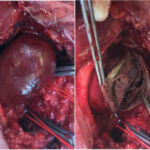

Στένωση Καρωτίδας

Η στένωση καρωτίδας είναι η στένωση της καρωτιδικής αρτηρίας λόγω συσσώρευσης αθηρωματικής πλάκας, η οποία μπορεί να μειώσει τη ροή αίματος προς τον εγκέφαλο και να αυξήσει τον κίνδυνο εγκεφαλικού επεισοδίου.